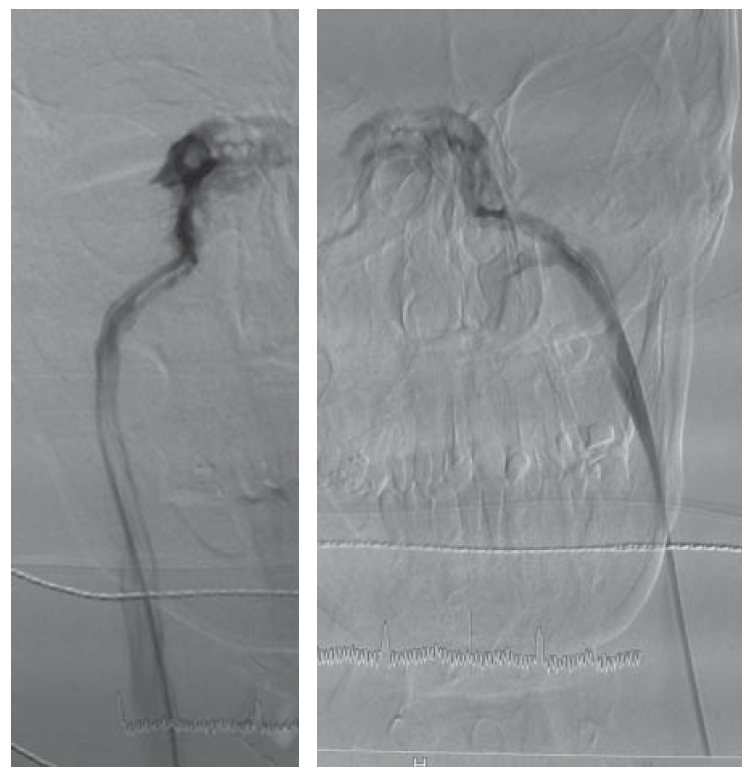

2. Fig. 1. Phlebogram of the inferior stony sines brain. | |